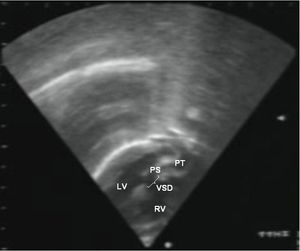

심장 초음파 검사는 심장의 구조와 기능을 정확하게 평가하는 초음파 검사이며, TGA의 특징을 보여줄 수 있다. 이 검사를 통해 TGA를 확진할 수 있다.[3]

평생 심장 전문의의 추적 관찰이 필요하다. 수술을 받은 대부분의 영아는 증상이 완화되고 정상적인 생활을 할 수 있다. 발생할 수 있는 잠재적인 합병증으로는 관상 동맥 문제, 심장 판막 문제 또는 불규칙한 심장 박동(부정맥) 등이 있다.[2]8. 추가 이미지

약어: LV 및 RV=좌심실 및 우심실, PT=폐동맥, VSD=심실 중격 결손, PS=폐동맥 협착.]]